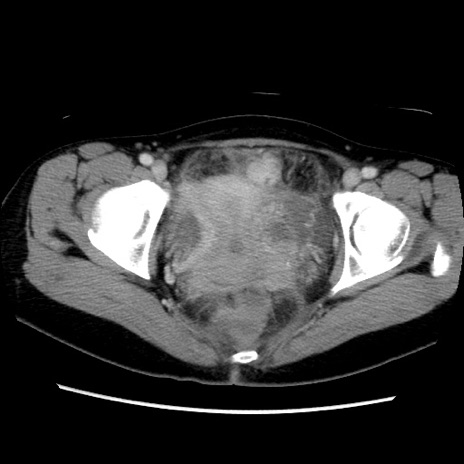

症例39(横断像)

【症例】40歳代女性

【主訴】上下腹部痛

【現病歴】2日目から下腹部痛あり。夜間は痛みで眠れなかった。昨日より上腹部痛と下痢が出現。臥位で痛みは軽快したため、休んでいた。本日になって臥位でも立位でも痛みが強くなってきたため救急要請。

【既往歴】子宮内膜症

【身体所見】部:平坦・軟、左上下腹部に圧痛あり、反跳痛あり。

【データ】WBC 21800、CRP 26.78